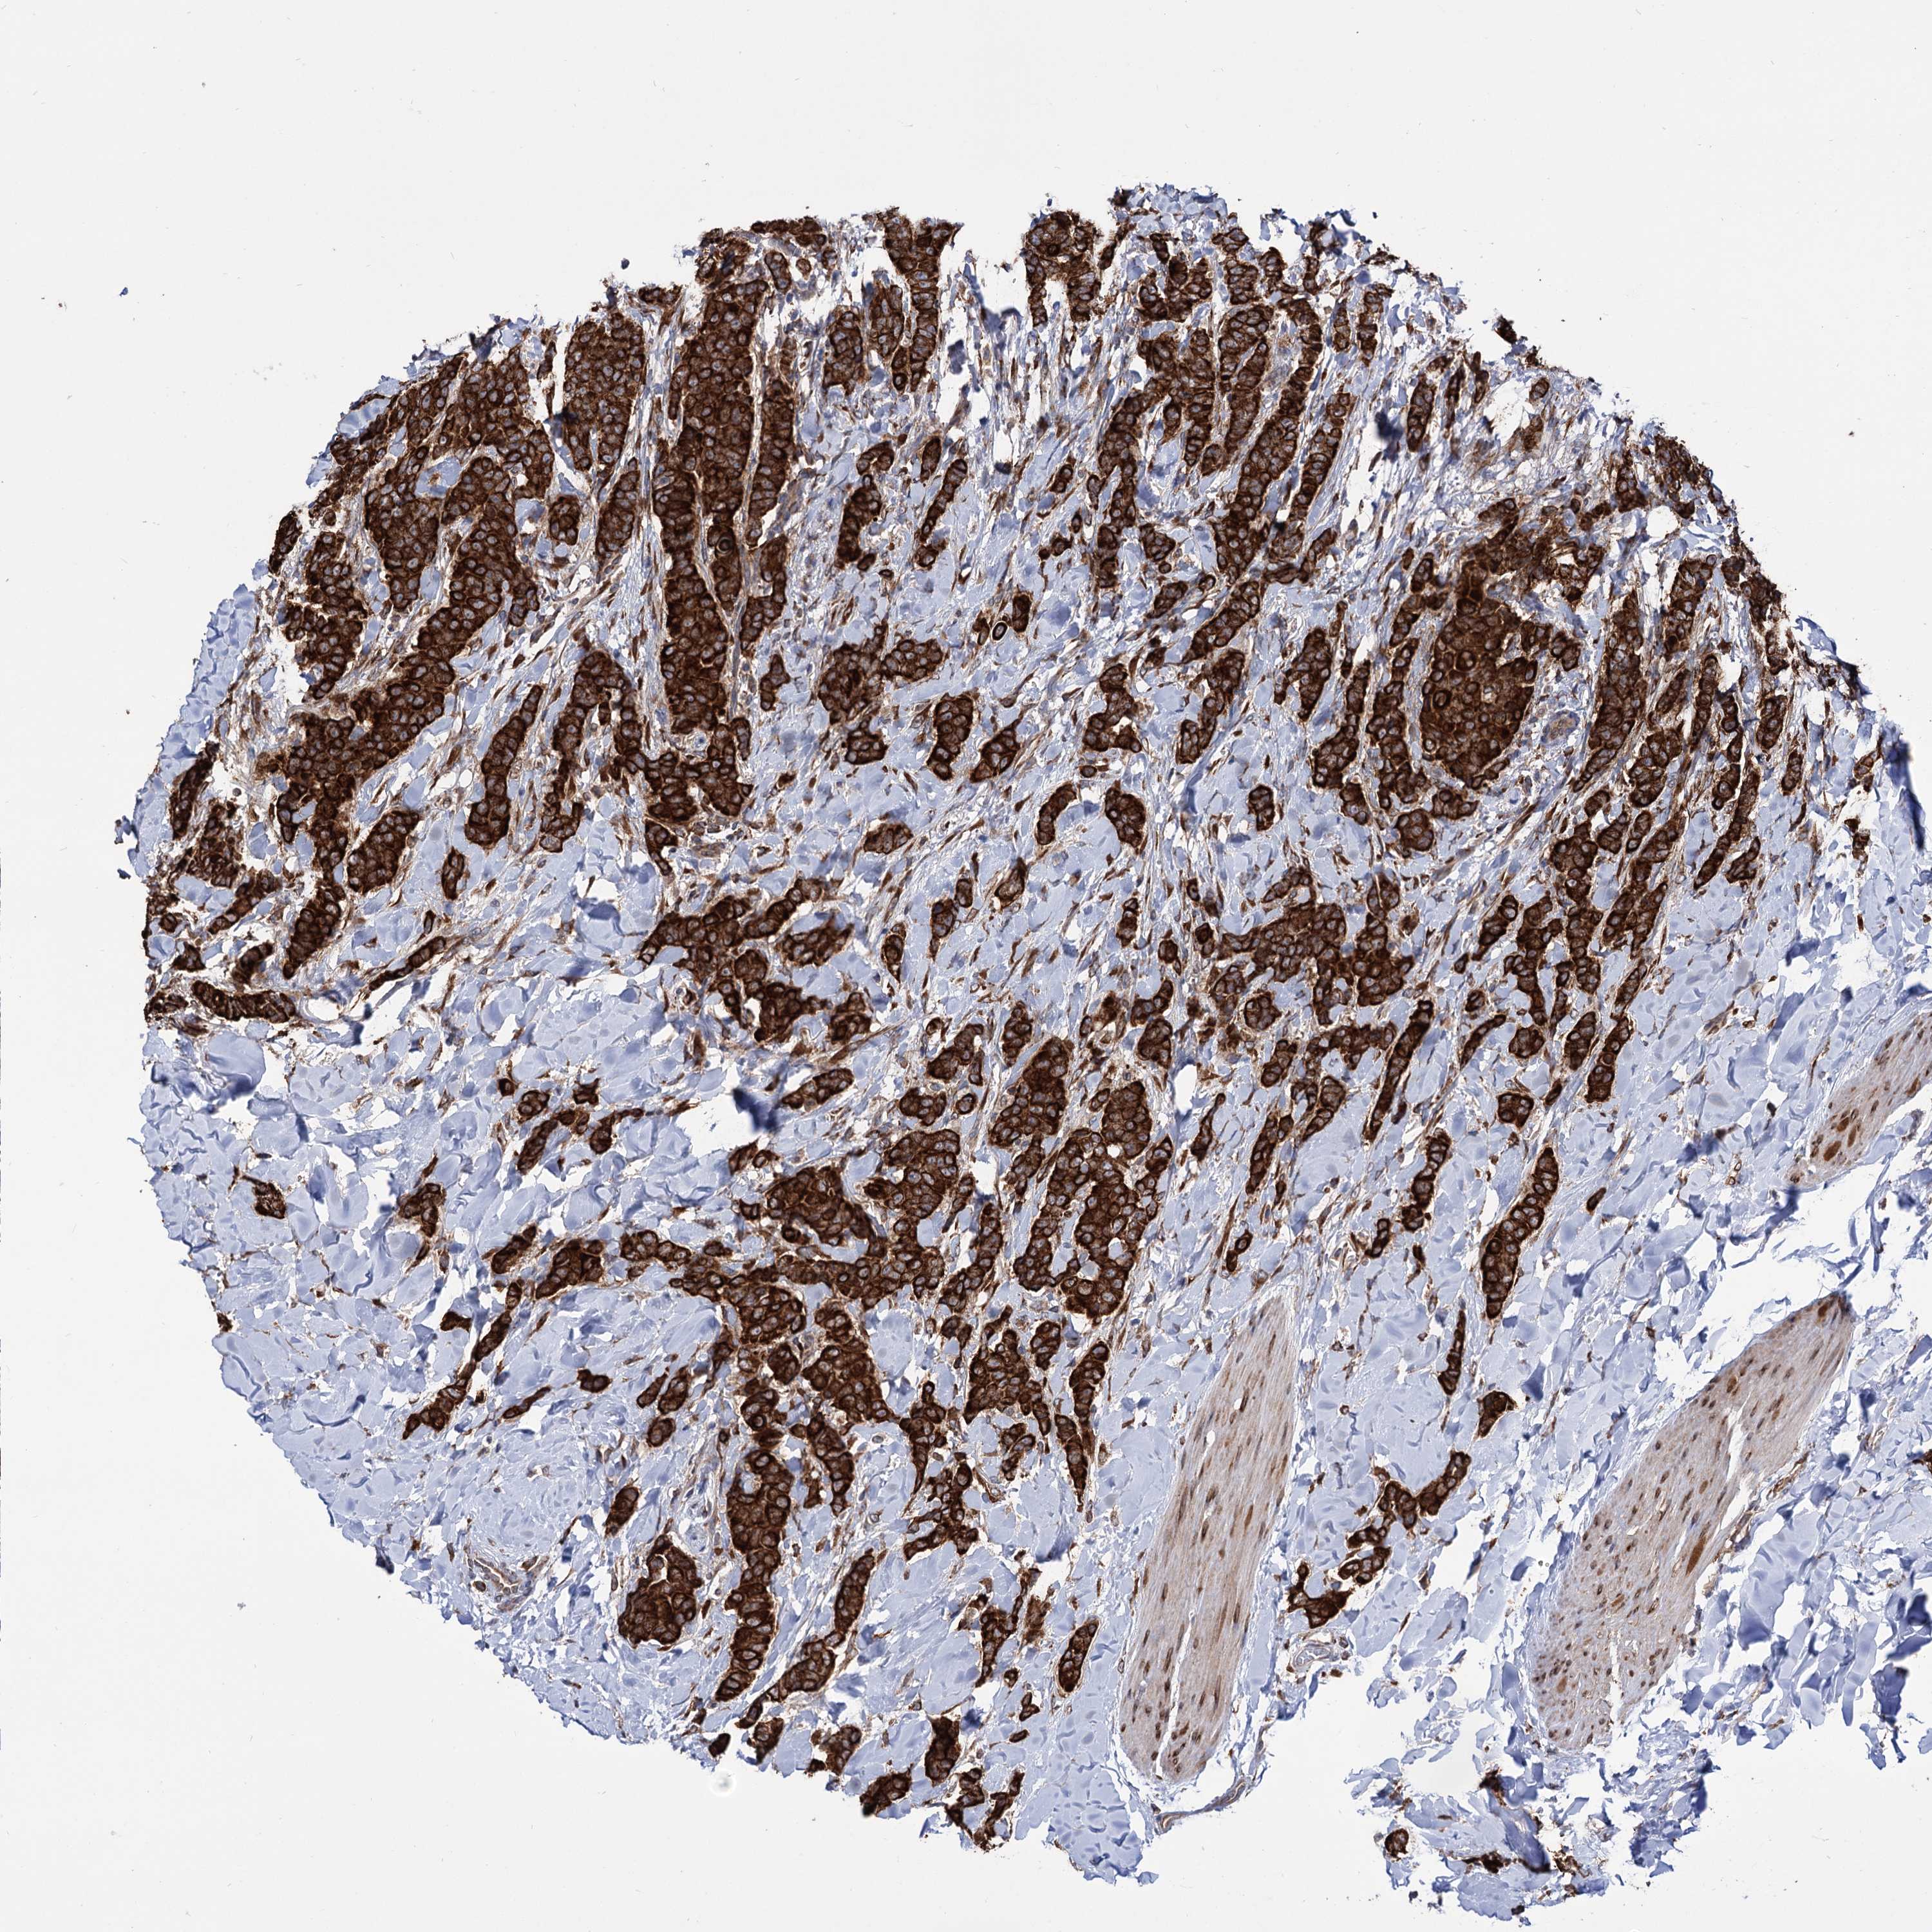

CANCER BREAST CANCER Show tissue menu

BRCA TCGA BRCA VALIDATION PROTEIN EXPRESSION